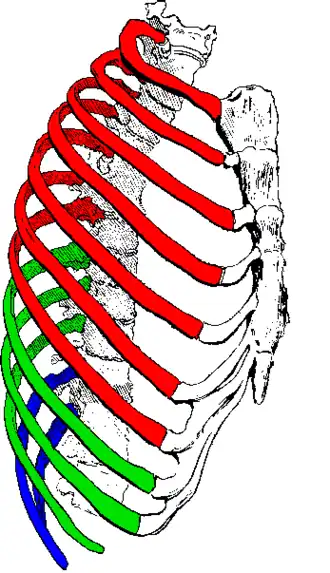

Les douze paires de côtes se répartissent en deux groupes :

- les sept premières paires, nommées côtes sternales ou vraies côtes, sont reliées directement au sternum par leur cartilage ;

- les cinq suivantes, dites côtes asternales, se répartissent en deux sous-groupes :

- les huitième, neuvième et dixième côtes, dites fausses côtes, ont leur cartilage uni à celui des côtes sus-jacentes ;

- les onzième et douzième côtes, dites côtes flottantes, se terminent par un cartilage libre.